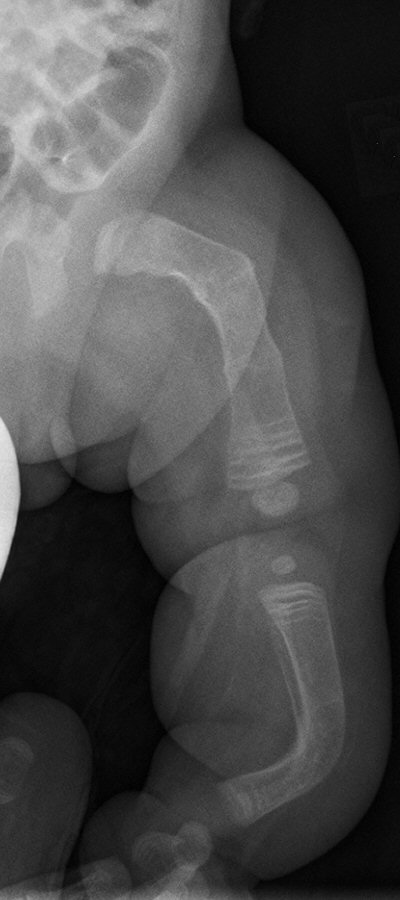

- Använd i första hand märgspikning med god upplinjering

- Profylaktisk märgspikning av långa rörben

Barn med osteogenesis imperfecta vid 6 månader, 2 år resp. 7 år